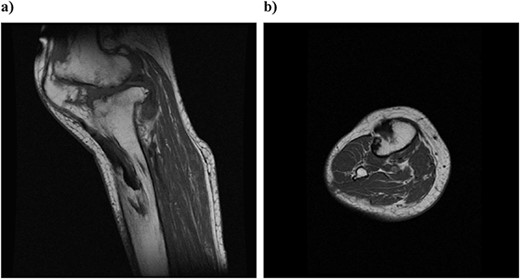

On physical examination, the patient extension and flexion were − 20° and 130°. A defect of the tibial tubercle was observed. The Knee Society (KS) score was 44 points, and the Knee Society function (KS-F) score was 70 points. A plain radiography showed valgus knee osteoarthritis assessed as Kellgren–Lawrence grade 4. In addition, a well-defined translucent image of bone appeared near the central part of the proximal tibia and no tibial tubercle could be observed (Fig. 1). Magnetic resonance imaging (MRI) of the right knee joint showed the patellar tendon appeared from the attachment on the patella with continuity to the tibial bone marrow in T1- and T2-weighted imaging (Fig. 2).

Preoperative simple magnetic resonance imaging: (a) lateral side and (b) axial morphism. T1- and T2-weighted images continuous from the patellar tendon attached to the patella both show continuity from the low signal area to the inside of the tibial bone marrow.